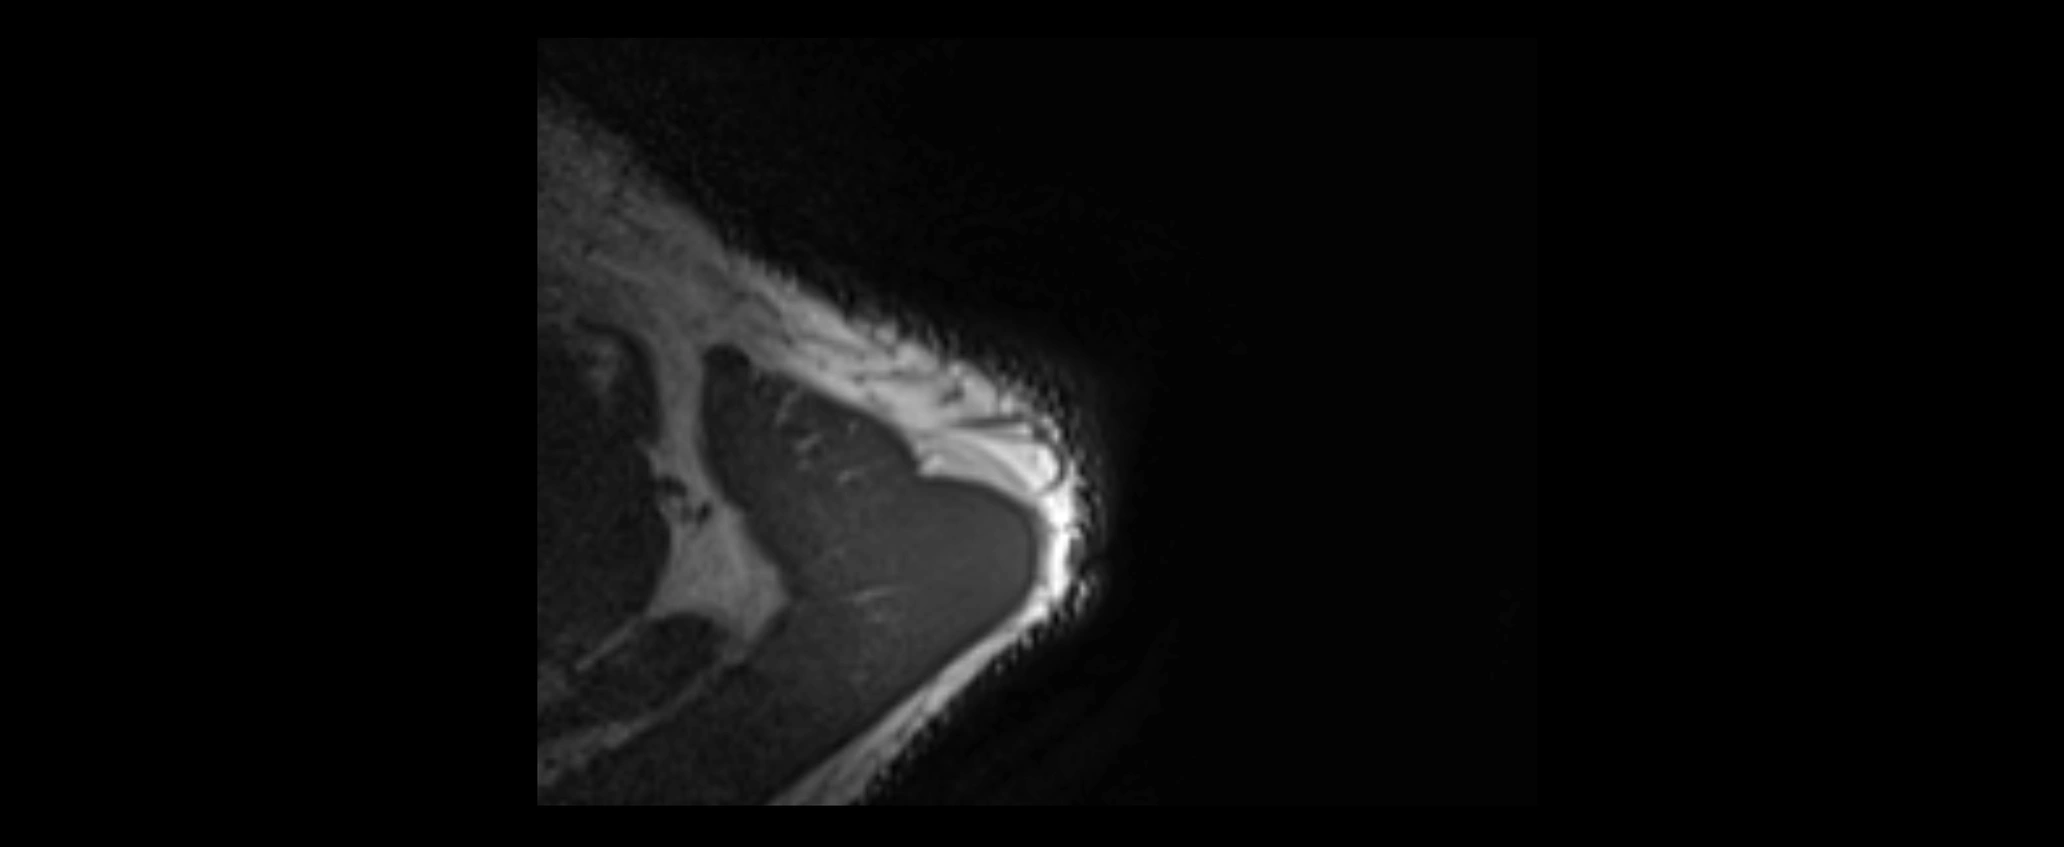

CT image

image

CT Appearance

Non-Contrast CT:

• Ligament: Not directly visualized due to small size and low density.

• Bony landmarks: Lateral clavicle and acromion clearly seen; cortical margins well defined.

• Pathology: Detects fractures, joint subluxation, osteophytes, and degenerative changes.

• Alignment assessment: Evaluates AC joint spacing and clavicular displacement.

Post-Contrast CT (standard):

• Ligament itself: Non-enhancing fibrous band.

• Inflamed capsule or soft tissue: May show enhancement.

• Useful for: Evaluating post-traumatic deformities, ossified ligaments, and chronic AC joint arthropathy.